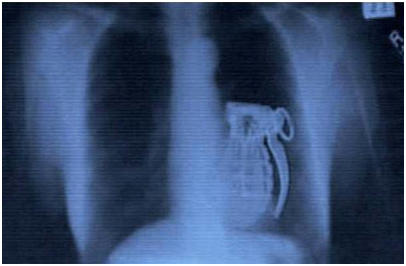

Ca amuzament, îi transmitem însă Gabrielei Firea că presa a consemnat ce obiecte ciudate au fost găsite în stomacul unor oameni neatenţi, publicînd chiar radiografiile realizate de medici. Iată, mai jos, cîteva dintre aceste obiecte, aşa cum apar în radiografii: un bec, un telefon, nişte magneţi şi chiar o… grenadă!